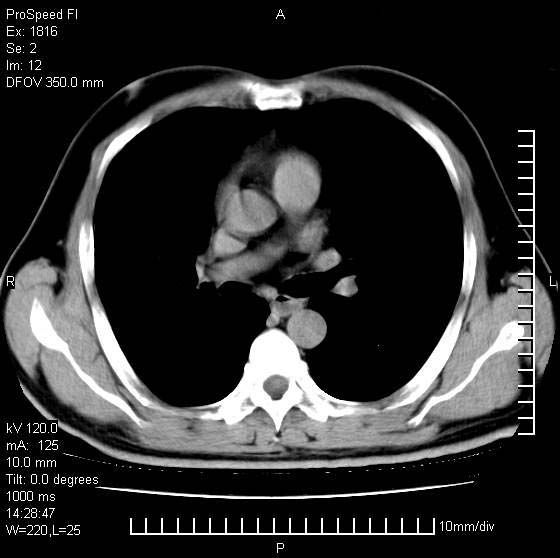

洞壁较厚内壁比较光整,两个病灶有关联性,纵隔淋巴结不大,考虑结核性空洞。

9年的结核应该呈现多形态病灶,该病例只能见到少许纤维索条影,似乎与结核的演变不太相符。空洞内壁不光整,外侧伴有胸膜粘连,考虑癌性空洞可能性大,期待结果。

考虑为右上肺癌。

周围型肺癌不能排除,建议手术治疗。